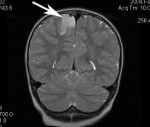

Основной метод диагностики ФКД - магнитно-резонансная томография. Она должна выполняться по специальному протоколу с толщиной срезов 1-2 Только такое тщательное сканирование способно выявить минимальные структурные изменения мозговой коры. В МРТ диагностике корковой дисплазии имеет значение опыт и квалификация рентгенолога. Поэтому при необходимости результаты исследования следует показать более опытному в этом вопросе специалисту.

К МРТ признакам ФКД относятся: локальная гипоплазия или утолщение коры, «смазывание» перехода между белым и серым веществом, изменённый ход извилин, повышенный МР-сигнал на ограниченном участке коры при исследовании в режимах Т2 и FLAIR. Каждый тип ФКД имеет свои особенности МРТ-картины.